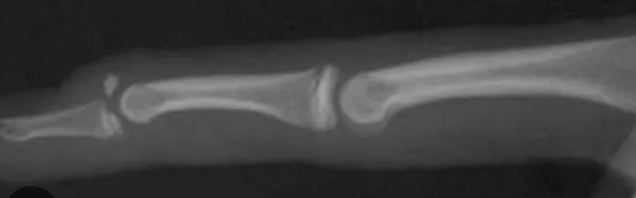

Que pedir en fracturas de falange y metacarpianos?

AP y lateral Falanges

AP y oblicua Metacarpianos

Fx falange

Fx de falange